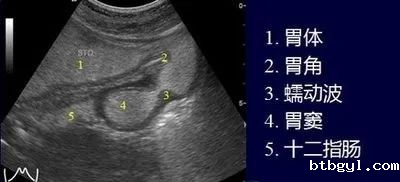

• 超声波精准成像:消除胃内气体干扰,清晰显示胃壁 5 层结构(黏膜层至浆膜层)及病变范围

• 动态观察全程无痛:无需麻醉、不插管,医生通过体外扫描即可实时评估胃蠕动、排空功能